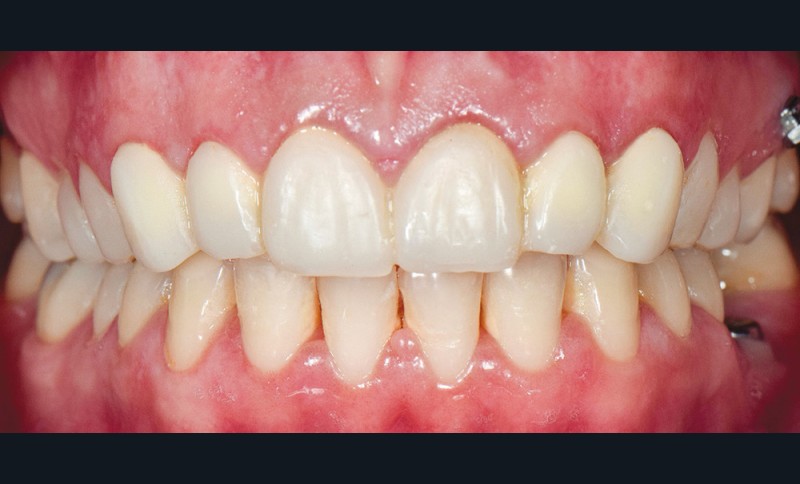

À l’examen endobuccal (fig. 1), une inflammation marginale et papillaire sur un parodonte de biotype fin est visible. Une gingivite généralisée induite par la plaque bactérienne est donc diagnostiquée.`

La ligne du sourire est inversée, malgré une perception atténuée par la présence de deux couronnes à armature zircone sur 11 et 21 réalisées une dizaine d’années auparavant. On note une irrégularité et une asymétrie de forme des festons gingivaux, ainsi qu’une dysharmonie de forme des incisives et canines quant à leur proportion.